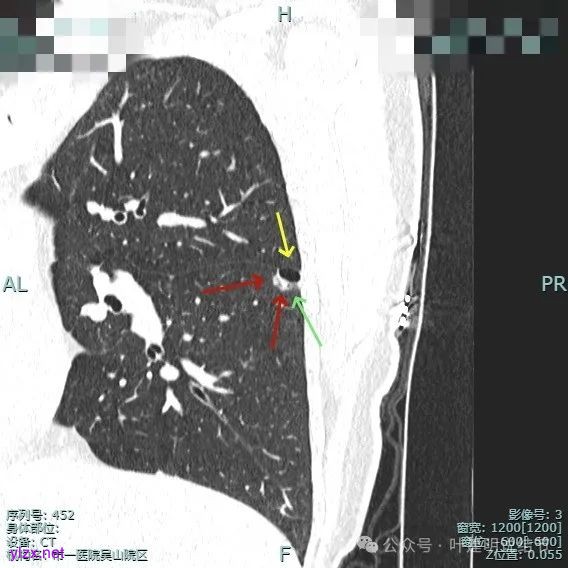

1、诊断问题:这是很典型的囊腔型肺癌,符合我自己之前提出的囊腔型肺癌三要素:(1)囊壁厚薄不均;(2)血管进入囊壁;(3)囊腔内壁不光滑(或再加止整体轮廓与边界较清)。而且由于囊壁实性成分明显,所以是有风险的,要及时干预处理。

2、囊腔型肺癌影像诊断的三要素(叶建明个人总结,仅供参考):囊壁厚薄不均、血管进入囊壁穿行、内壁不光滑(或再加上整体轮廓与边界清楚);